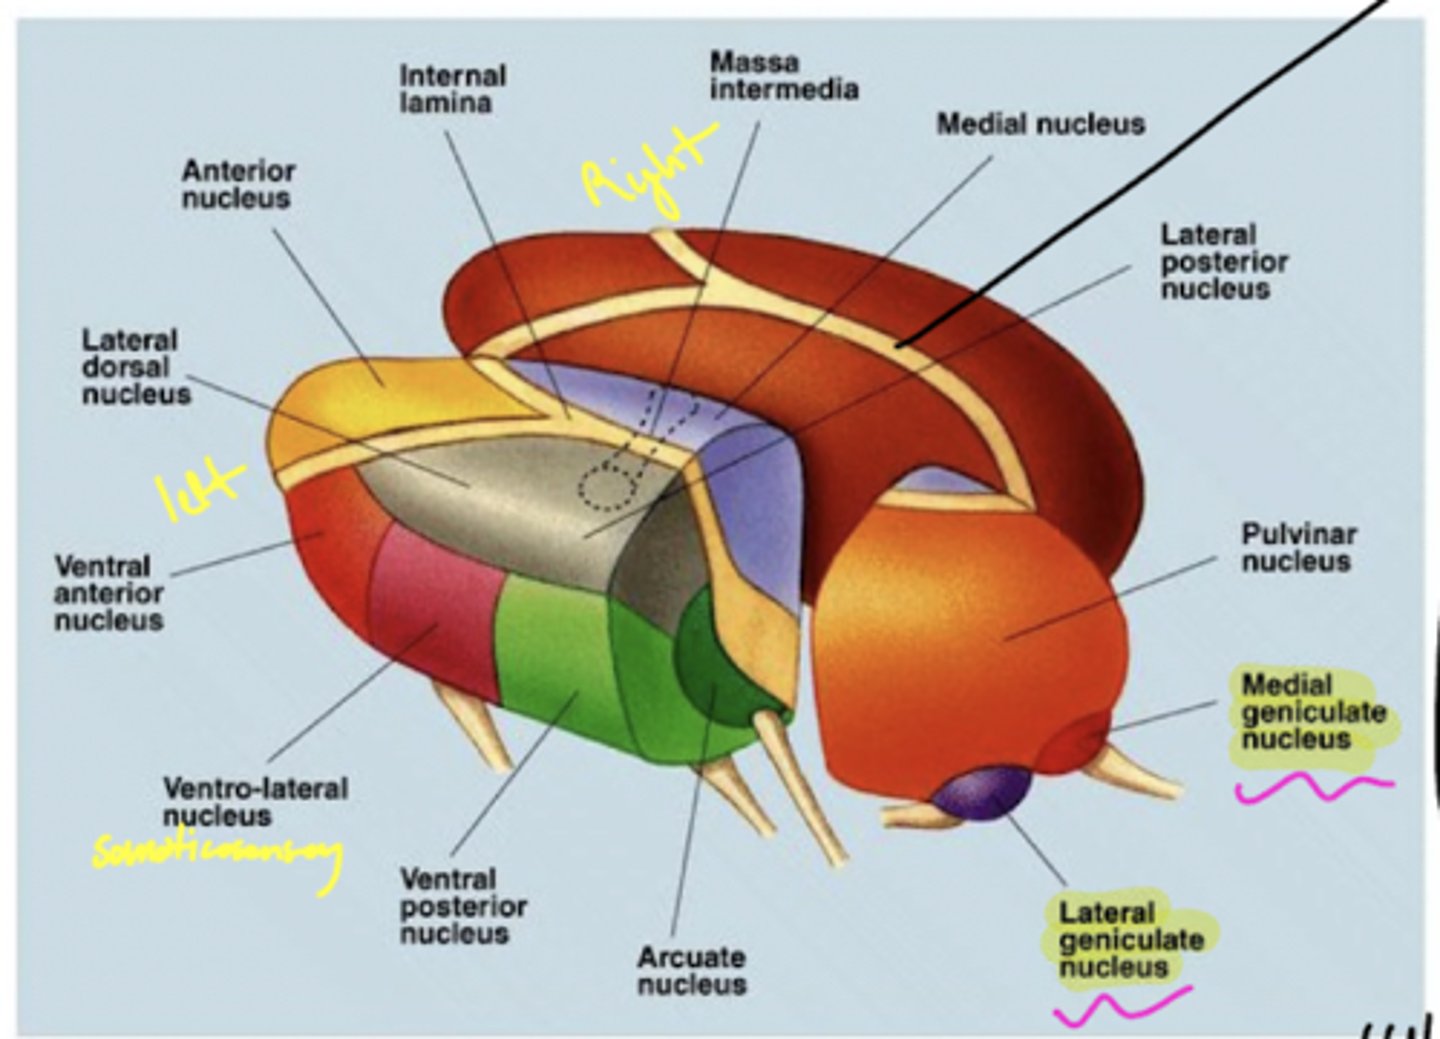

What are the three nuclear complexes of the thalamus?

1. anterior nuclei

2. medial nuclei (connected by massa intermedia)

3. lateral nuclei

What is the medial nuclei connected to?

1. each other via massa intermedia

2. prefrontal cortex

why prefrontal cortex? -- afferent for medial/lateral portions of the medial nucleus

What are the nuclei (discussed) of the lateral nuclei of the thalamus?

1. LGN

2. MGN

3. pulvinar

4. VPL

5. VPM

What are the nuclei (discussed) of the lateral nucleus of the thalamus?

1. LGN

2. MGN

3. VPL (ventral posterolateral nucleus)

4. VPM (ventral posteromedial nucleus)

5. pulvinar

Where does the LGN project?

17 -- primary visual cortex

Where does the MGN project?

41 -- primary auditory cortex

Where does the VPL project?

3, 1, 2 -- somatosensory cortex (body)

Where does the VPM project?

3, 1, 2 near the lateral fissure -- somatosensory cortex

processing of the face

What is the pulvinar of the thalamus?

largest association nucleus of the thalamus

What is afferent to the pulvinar of the thalamus?

superior colliculus (and its association areas)

Where does the pulvinar of the thalamus project?

secondary visual areas (and association areas of the parietotemporal region)

What are the functions of the pulvinar of the thalamus?

1. attention to visual stimuli (even in peripheral vision)

2. eye movements